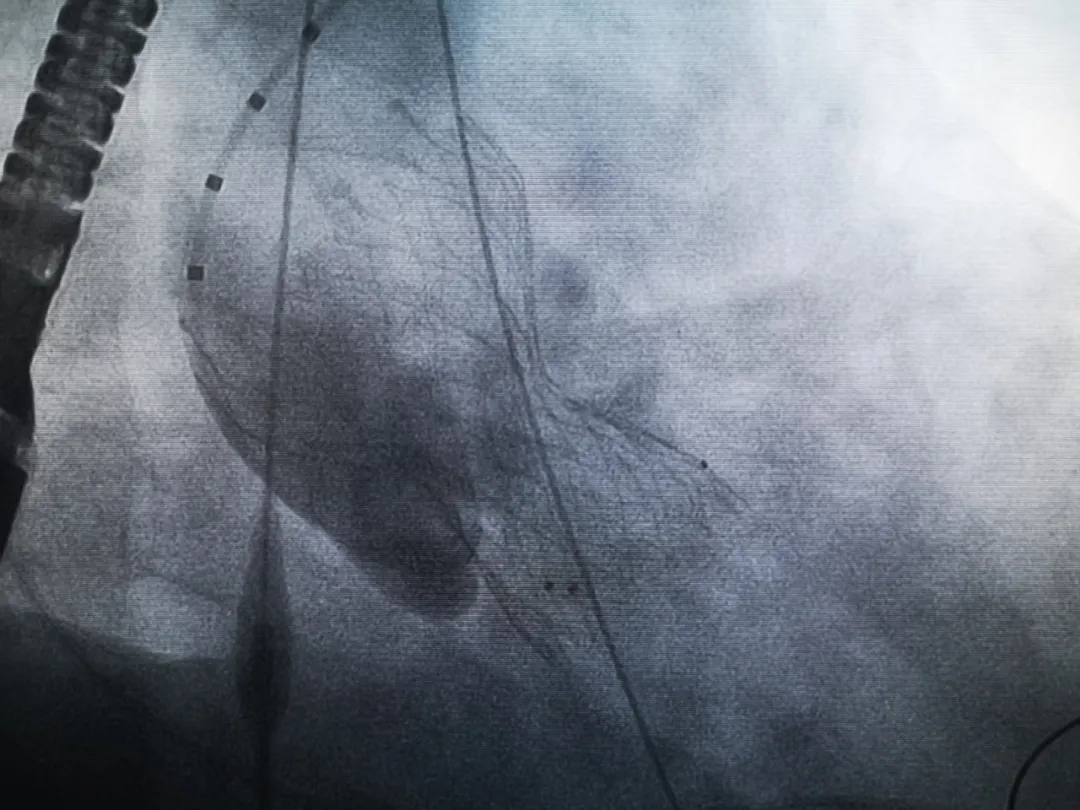

王子的手術(shù)被安排在周五。術(shù)前一天,TAVR團隊再次碰頭討論,從麻醉中血壓控制、球囊擴張、瓣膜釋放,到各種可能突發(fā)狀況的應對,都提前制定了方案。尤其是瓣膜鈣化極為嚴重,對于擴張球囊型號的選擇、擴張的力度以及瓣膜植入后瓣周漏的發(fā)生預測,都具有很大挑戰(zhàn)。然而,如果沒有這些挑戰(zhàn),他又何必選擇我們呢!

手術(shù)過程緊張而有序,心臟沒有停跳,也沒有太大的血壓波動;球囊擴張的恰到好處,瓣膜釋放之后超聲醫(yī)生的評估是至關(guān)重要的,因為我們提前就準備了后擴張,也準備了瓣中瓣,甚至還準備了瓣周漏封堵。所幸的是,超聲診療中心劉夢梅醫(yī)生說:沒有返流、沒有瓣周漏,瓣膜形態(tài)良好,跨瓣壓差約17mmHg(相較于術(shù)前的87mmHg還是可以接受的)。瓣膜置入的成功并不是慶祝的時候,從戰(zhàn)場撤退仍然需要謹慎。由于王子特別胖,腹股溝區(qū)脂肪尤為肥厚,在股動脈插管拔除、確認搏動正常之后,便逐層縫合。同時為了美觀、縫合之后不至于鼓個包出來,我們又仔細剪除了部分脂肪。術(shù)后次日,王子便可以下床活動了。